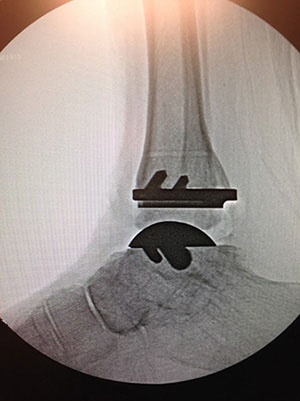

Shasta Ortho Offers NEW Total Ankle Replacement System

Are you suffering from chronic ankle pain or have suffered a serious ankle injury and are located in the Northern California area? If you’re looking for a long-term solution for your ankle pain or ankle injury, Shasta Orthopaedics in Redding, California has some exciting news in ankle replacement! Dr. Jason Nowak is one of the first surgeons in the nation who is now using a cutting edge new total ankle system called the INFINITY® Total Ankle Replacement (TAR) System. The new system is less invasive for surrounding joints than previous ankle replacement options.